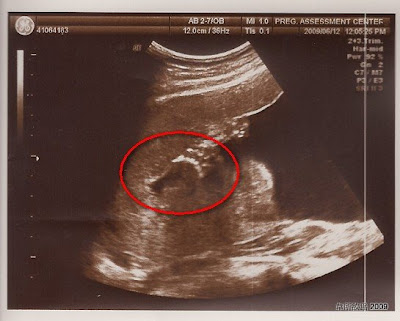

不管如何,來看看小黃瓜的高層次超音波檢查吧:)

↓醫生一說要照手掌數手指頭,小黃瓜就伸出手跟大家Say Hello了

↓另外一隻手

因為小黃瓜非常配合醫生的檢查,醫生想照哪裡都沒遇到太大困難,所有檢查在30分鐘左右就結束了,最後醫生還照了兩張臉部特寫給我們。照片可以參考

小黃瓜長相大公開